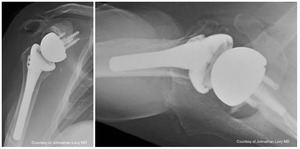

Case one is a 58-year-old male who is an avid golfer with long standing right shoulder pain. Surgical history includes previous Bristow procedure 30 years prior. Current Subjective Shoulder Value (SSV) is 30% and pain is 8/10 at baseline. Active range of motion was 110° of forward flexion, -10° of external rotation and interna rotation to the lateral buttock. Radiographs (Figure 1) and computed topography (CT) scan (Figure 2) show retained implants with loss of joint space, glenoid retroversion, and significant posterior humeral head subluxation. The patient had failed conservative management and was indicated for arthroplasty. Due to significant posterior bone loss and retroversion, an augmented anatomic component was selected for this patient. Radiographs at one year show a well seated glenoid component with restoration of the joint line and a centered humeral head (Figure 3). At five years, SSV had improved to 95% with excellent clinical motion (Figure 4).